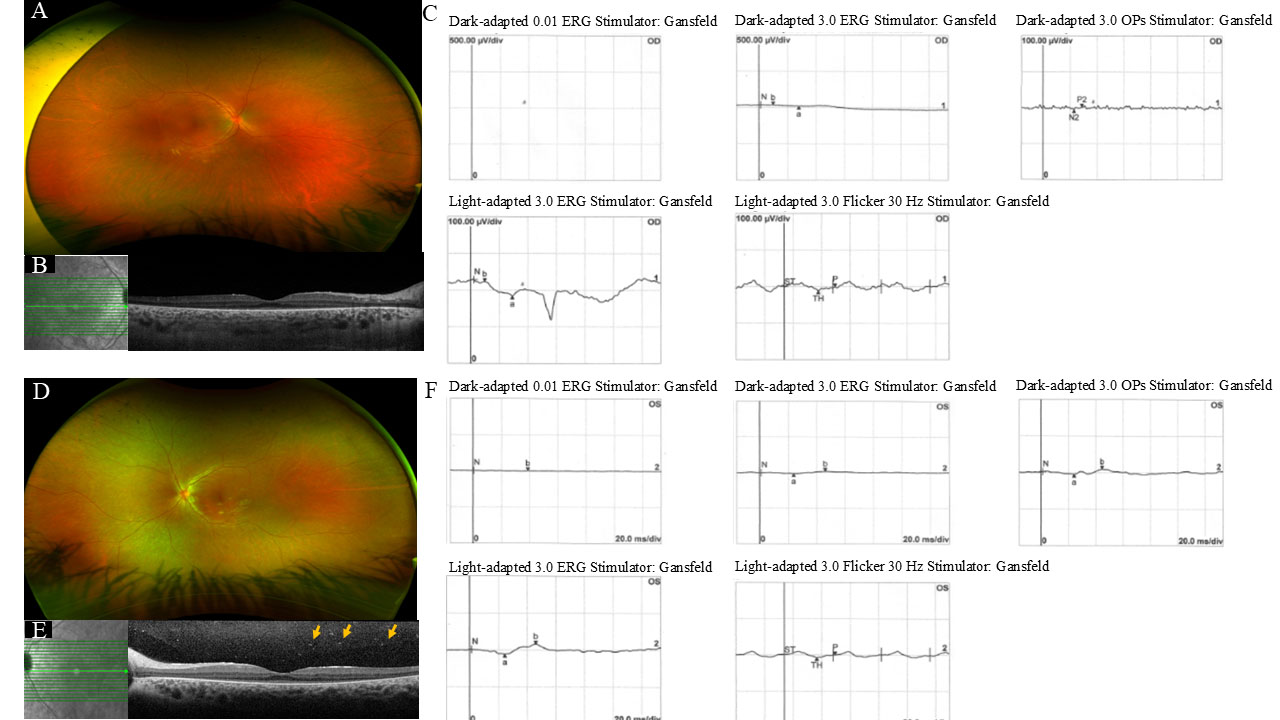

Figure 5. Images and full-field electroretinogram of Case 6 with RPE65 gene mutation. Case 6 shows a proband with mutation c.11+5 G>A and c.1520C>T; p.(Ala507Val) at the age of 12 years. The fundus

(A and D) shows diffuse pigmentary changes in the retina, and blood vessels, optic disc, and macula apparently preserved in both eyes

(OU). OU optical coherence tomography (B and E) shows subfoveal outer retina preserved, and perifoveal atrophy with loss of the ellipsoid zones. In the left eye (OS) vitreous

cavity, there are signs of vitreous degeneration (highlighted by the orange arrow). The full-field electroretinogram shows

minimal rod and cone responses in OU (C and F).